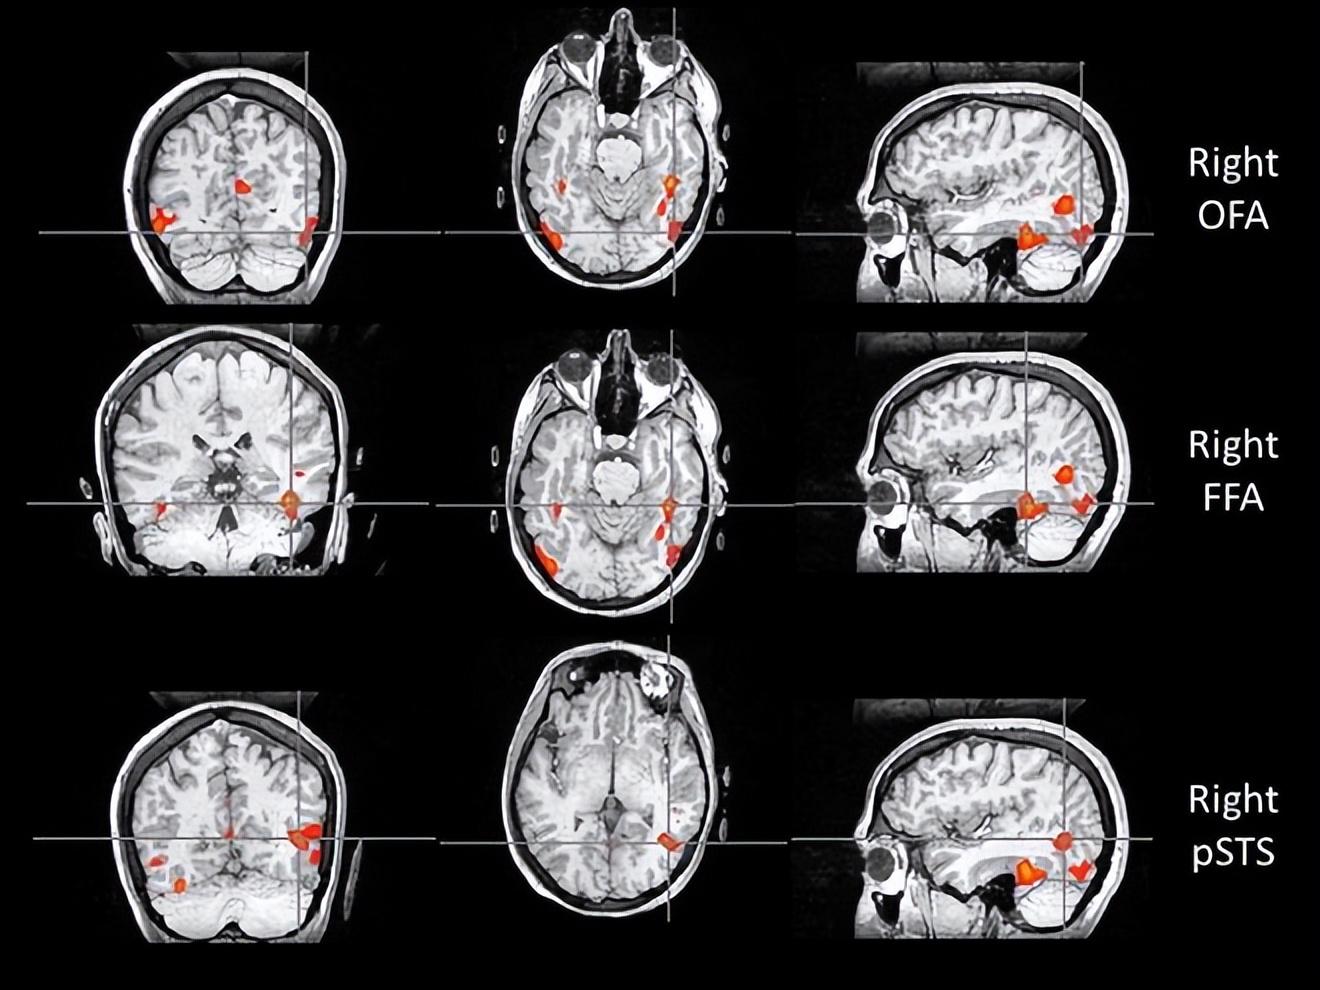

比如,位於枕葉的枕葉面孔區(Occipital Face Area, OFA),就像識臉網絡的“先鋒部隊”。它專門處理眼睛、鼻子和嘴巴等五官“零部件”。當一張臉出現在我們眼前時,OFA 只需 約 100 毫秒 就能被激活,迅速對局部特徵進行拆解,並將信息傳遞給 FFA 和上顳溝(Superior Temporal Sulcus, STS)。所以如果 OFA 出現問題,識別人臉就會變的很困難。

如果說 OFA 的作用是拆解五官,那麼 STS 則更像是一個“動態解碼器”。它對靜態的面孔特徵興趣不大,卻對動態特徵極爲敏感,尤其擅長捕捉一顰一笑、眼神轉動、嘴脣開合等細微變化。

正因爲有 STS 的參與,我們不僅能認出“這是誰”,還能理解“他在表達什麼情緒”“注意力投向哪裏”,甚至在一定程度上推測對方的意圖。STS 的參與也解釋了爲什麼比起靜態照片,在現實生活或視頻中,我們更容易認出熟人。

與認臉有關的三個核心腦區,自上而下依次爲:OFA(枕葉面孔區)、FFA(梭狀回面孔區),以及 STS(上顳溝)。圖片來源:doi: 10.1007/s00221-011-2579-1